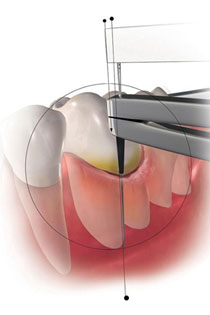

Neue Special-Site zu unserer neuen 3D-Endodontie Software: Besser, schneller und einfacher behandeln!

Eine Endodontie Behandlung (Wurzelkanalbehandlung) ist ein elementarer Bestandteil in unserer täglichen Behandlungspraxis in der modernen Zahn­erhaltungs­kunde. Das Ziel, der Gemeinschaftspraxis für Zahn-, Mund- und Kieferheilkunde Dr. Gorden & Dr. Poll in Dortmund, ist der möglichst lebenslange Zahnerhalt. Dazu gehört eine perfekte und sichere Zahnbehandlung. Lernen Sie die Vorteile unserer neuen 3D-Endodontie Software auf unserer Special-Site kennen!

Foto: © Densply Sirona